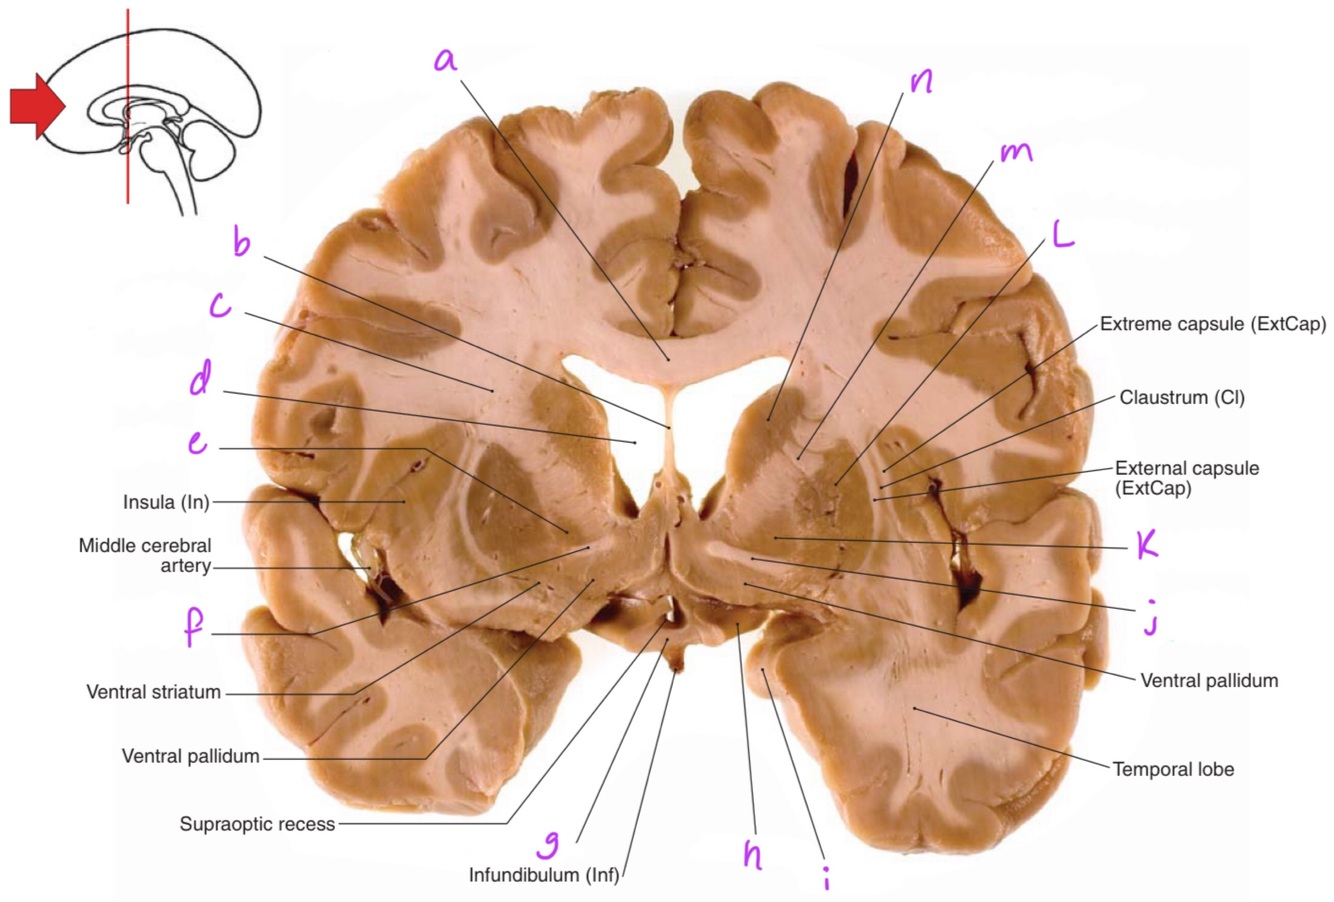

1

a

body of corpus callosum

b

Anterior horn of lateral ventricle

3

c

6

f

7

g

8

h

Q

10

11

12

d

13

e

14

15

16

17

i

18

j

19

k

20

L

21

m

22

n